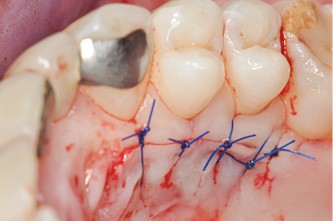

Une chirurgie retransmise en direct depuis l’hôpital Bretonneau APHP sera proposée, illustrant le traitement de récessions dans le secteur antérieur esthétique.